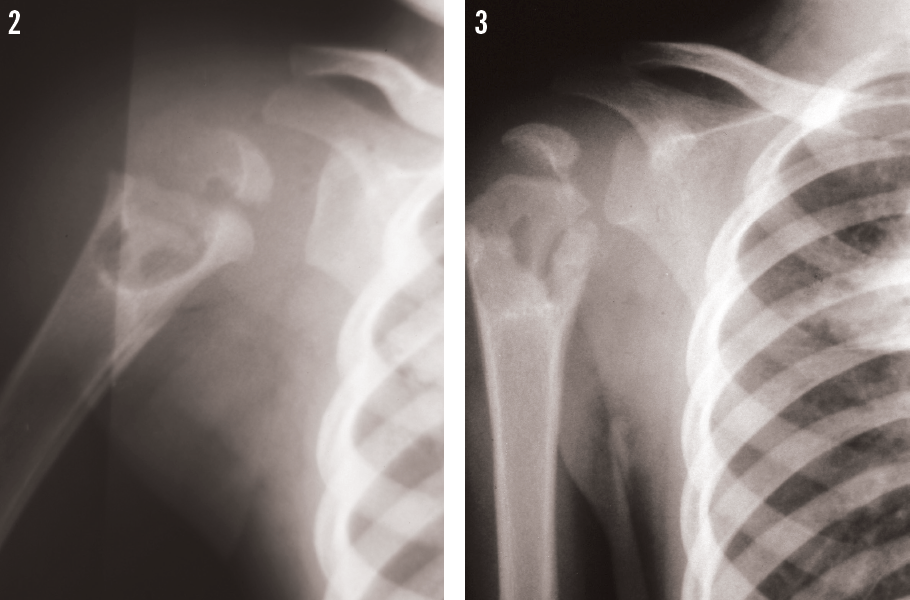

A follow-up shoulder radiograph at 1 month demonstrated improvement of the lytic lesion (Figure 3). He eventually received 2 months of the 3-drug regimen—isoniazid, rifampin, and pyrazinamide—and completed a year of therapy with isoniazid and rifampin under the supervision of the county TB program’s direct observation therapy, and he did very well.